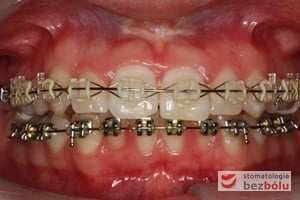

Pacjentka lat 22 zgłosiła się do naszej placówki celem podjęcia leczenia ortodontycznego. Głównym oczekiwaniem pacjentki była poprawa estetyki uśmiechu oraz brak ekstrakcji zębów na drodze do jej uzyskania. Ze względu na liczne stłoczenia zębów w górnym i dolnym łuku, dość duży materiał zębowy w porównaniu z bazą kostną, a także zgryz przewieszony boczny prawostronny po dokładnej analizie cefalometrycznej oraz analizie modeli diagnostycznych zastosowano leczenie bezekstrakcyjne z wykorzystaniem strippingu jako alternatywy dla usuwania zębów, mającego na celu uzyskanie miejsca w łuku na uszeregowanie zębów. Po fazie aktywnego leczenia trwającego 18 miesięcy zastosowano leczenie retencyjne w postaci szyny retencyjnej w łuku górnym oraz retainera stałego w łuku zębowym dolnym klejonego od kła do kła.